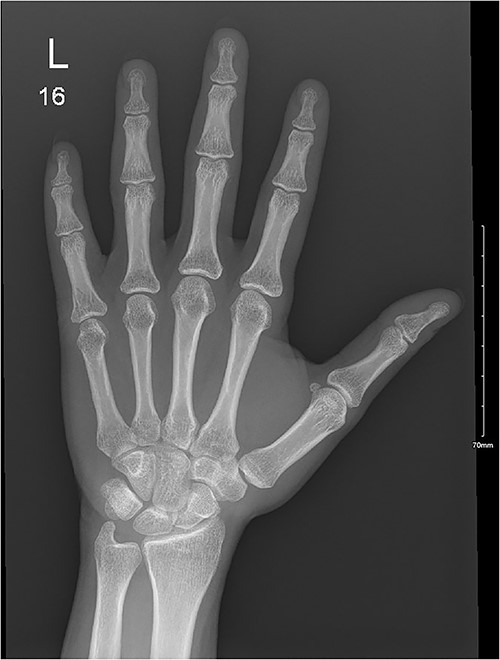

A 28-year-old female came to the emergency room (ER) following an MVA with airbag-deployment 5 days before presentation. Examination revealed tenderness at the base of the proximal fifth finger. The ROM of the affected digit was limited, but the neurovasculature as well as flexor digitorum profundus and flexor digitorum superficialis function were intact. X-ray of the hand showed a minimally displaced fracture at the base of the proximal fifth phalanx extending into the articular surface (Fig. 5). The decision was made to manage the patient conservatively by applying an ulnar gutter splint, which was then changed to a volar splint when the patient was followed-up in the clinic a week later. When the patient was last seen, the patient had limited ROM, and the tenderness had resolved. Imaging showed evidence of ongoing healing (Fig. 6).

A minimally displaced fracture at the base of proximal fifth phalanx extending into the articular surface.

Ongoing healing is seen in the distal radius fracture. The fracture line is barely visible.